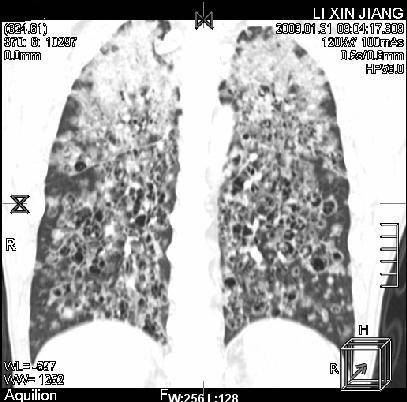

标题: CT18283:呼吸困难,明显喘息样呼吸 [打印本页]

呼吸困难,明显喘息样呼吸2个月

间质性肺病!还能用多久?

多为霉菌感染。

考虑两肺机遇性感染。

卡孢子虫肺炎(建议试验室查hiv,呼吸道分泌物找卡孢子虫)

机遇性感染,间质性病变

考虑:间质性病变伴两肺机遇性感染。

间质纤维化伴支扩。原因?

支持考虑:间质性病变伴两肺机遇性感染。

考虑 间质性病变伴两肺机遇性感染。